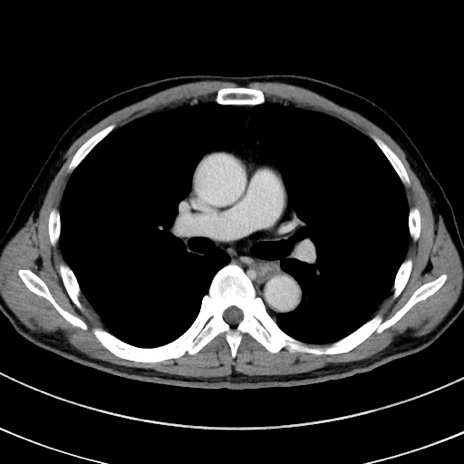

症例8(横断像)

【症例】 60歳代男性

【主訴】 黒色吐物

【現病歴】 4日前から嘔気自覚、2日前の朝食後にも嘔気あり、自分で手で嘔吐反射起こし嘔吐したところ血が混ざっていたため受診。

【既往歴】 5年前汎発性腹膜炎を伴う急性虫垂炎で手術、高血圧、前立腺肥大症、高脂血症

【身体所見】 腹部正中に手術癩痕あり 腹部平坦・軟圧痛なし膨満感あり

【データ】WBC 8400、CRP 4.54